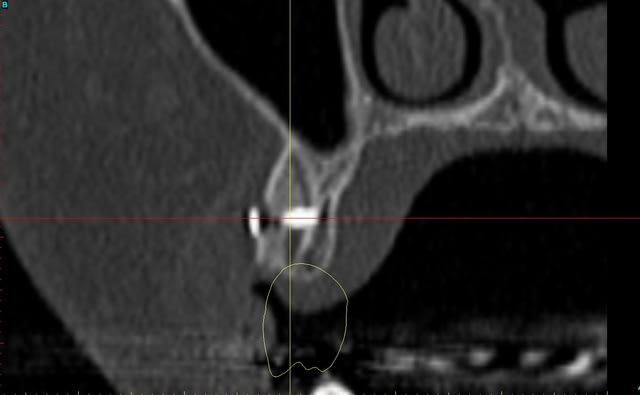

Dar axial lebnbu - Eugenol

Dar axiali qui1is - Eugenol

Dar11 cyo3el - Eugenol

Dar13 alznrp - Eugenol

Dar13i aujibg - Eugenol

Dar14 actm24 - Eugenol

Dar15 zvi82y - Eugenol

Dar23i g6nxds - Eugenol

Dar24 vzfroa - Eugenol

Dar25 lcptyk - Eugenol

Dar 3d xkb3uv - Eugenol

Dar  3di ngfcc4 - Eugenol

Dar  3dl fwmdk6 - Eugenol

image 8, il semble y avoir une zone entre le greffon et l'os ?

C'est intégré ?